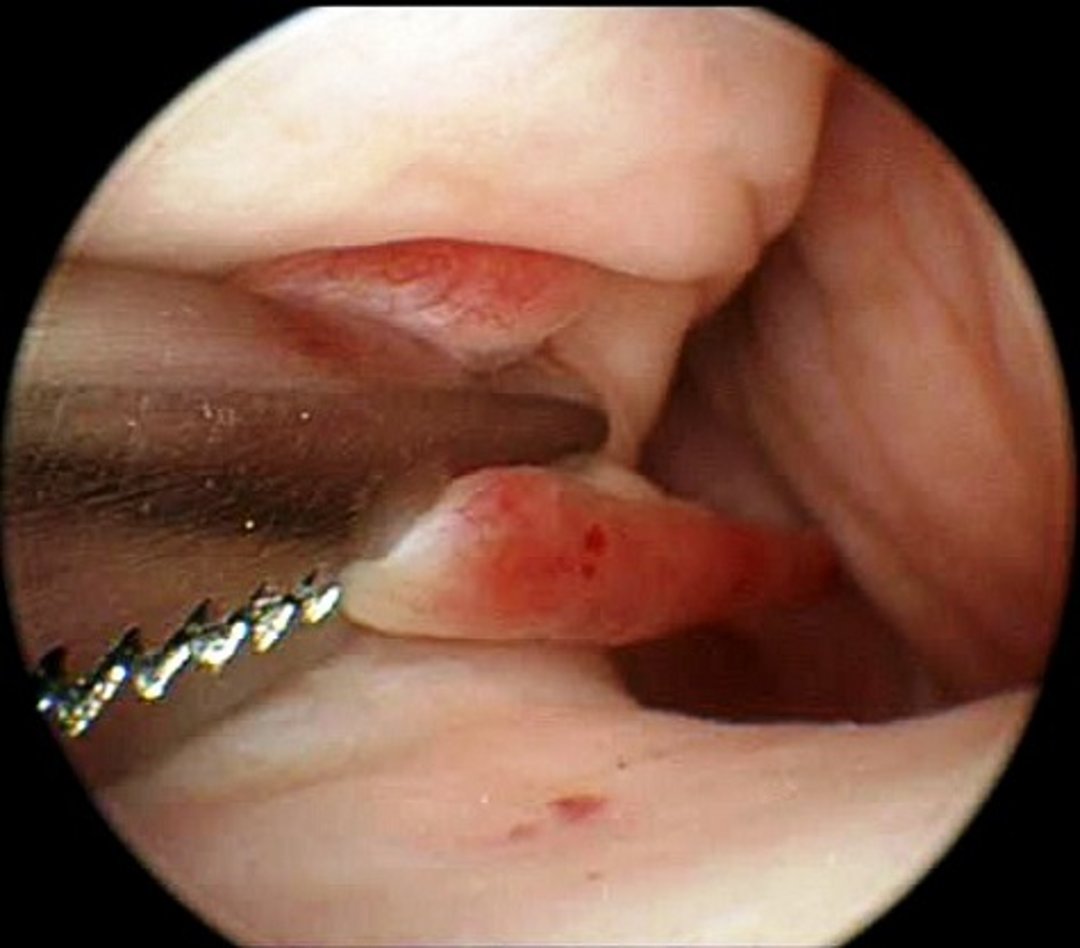

Intraoperative photograph demonstrating septate vaginal strand revision performed during a vaginoscopy.

Courtesy of Dr. Autumn Davidson.